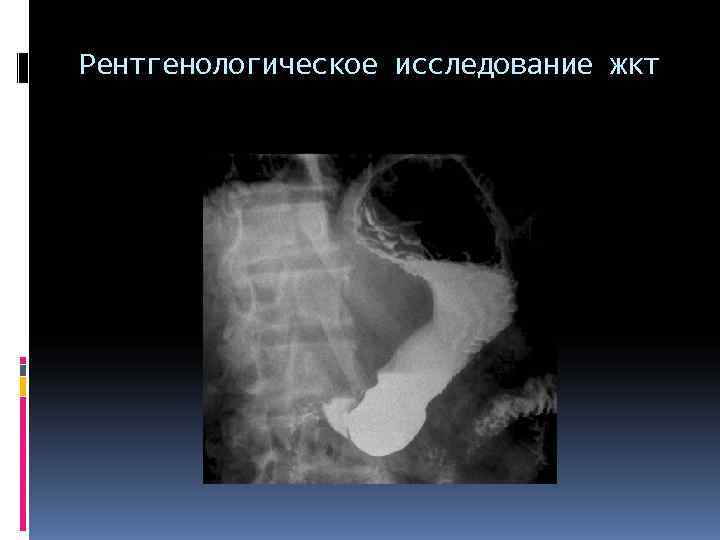

Рентгенологическое исследование жкт

Рентгенологическое исследование желудка Контрастное вещество заполняет межскладочные промежутки, и на экране (снимке) появляется изображение складок слизистой оболочки При этом определяют положение, форму и величину желудка, его тонус, характер тонусов, смещаемость, наличие болевых точек, двигательную функцию (перистальтика, «игра» привратника, ход опорожнения). Далее контрастное вещество переходит в двенадцатиперстную кишку.

Исследование желудка и 12 перстной кишки Оценивают • скорость равномерность движения контрастной массы • положение • форму • диаметр • контуры тени органа • Рельеф складок • слизистой пищевода, желудка • функцию пищеводно- желудочного преддверия (диафрагмального жома, кардии).